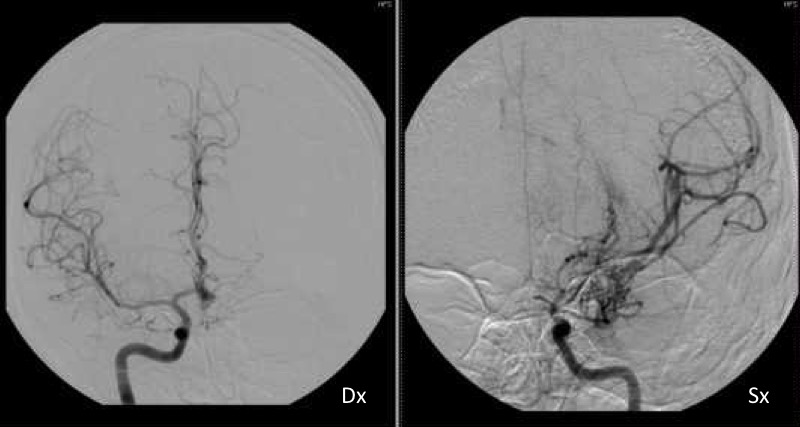

Il giorno successivo ritorna in Accettazione per il peggioramento della sintomatologia. La RM encefalo urgente descrive: “Nella sequenza angio-RM arteriosa intracranica l’arteria carotide interna sinistra dal tratto cervicale distale sino al sifone carotideo ha calibro uniformemente ridotto rispetto alla controlaterale senza segni di dissezione recente, l’arteria cerebrale media di questo lato si visualizza nel tratto M1 prossimale di aspetto sottile e nel tratto M1 distale non si osserva flusso, presenza di sottili strutture vascolari tortuose nella scissura silviana adiacente, i rami di divisione dell’arteria cerebrale media a valle sono assottigliati rispetto ai controlaterali; i reperti sono suggestivi di un quadro Moyamoya-like” (Figure 1 e 2).

Il ragazzo veniva pertanto ricoverato presso il nostro reparto, dove è stata iniziata terapia con acido acetilsalicilico (150 mg x 2 per i primi 4 giorni; successivamente 150 mg una volta die), ed è stata eseguita una angiografia cerebrale che confermava la stenosi a carico del tratto prossimale dell’arteria cerebrale media e la presenza di circoli collaterali di compenso, confermando così il quadro di Moyamoya-like.